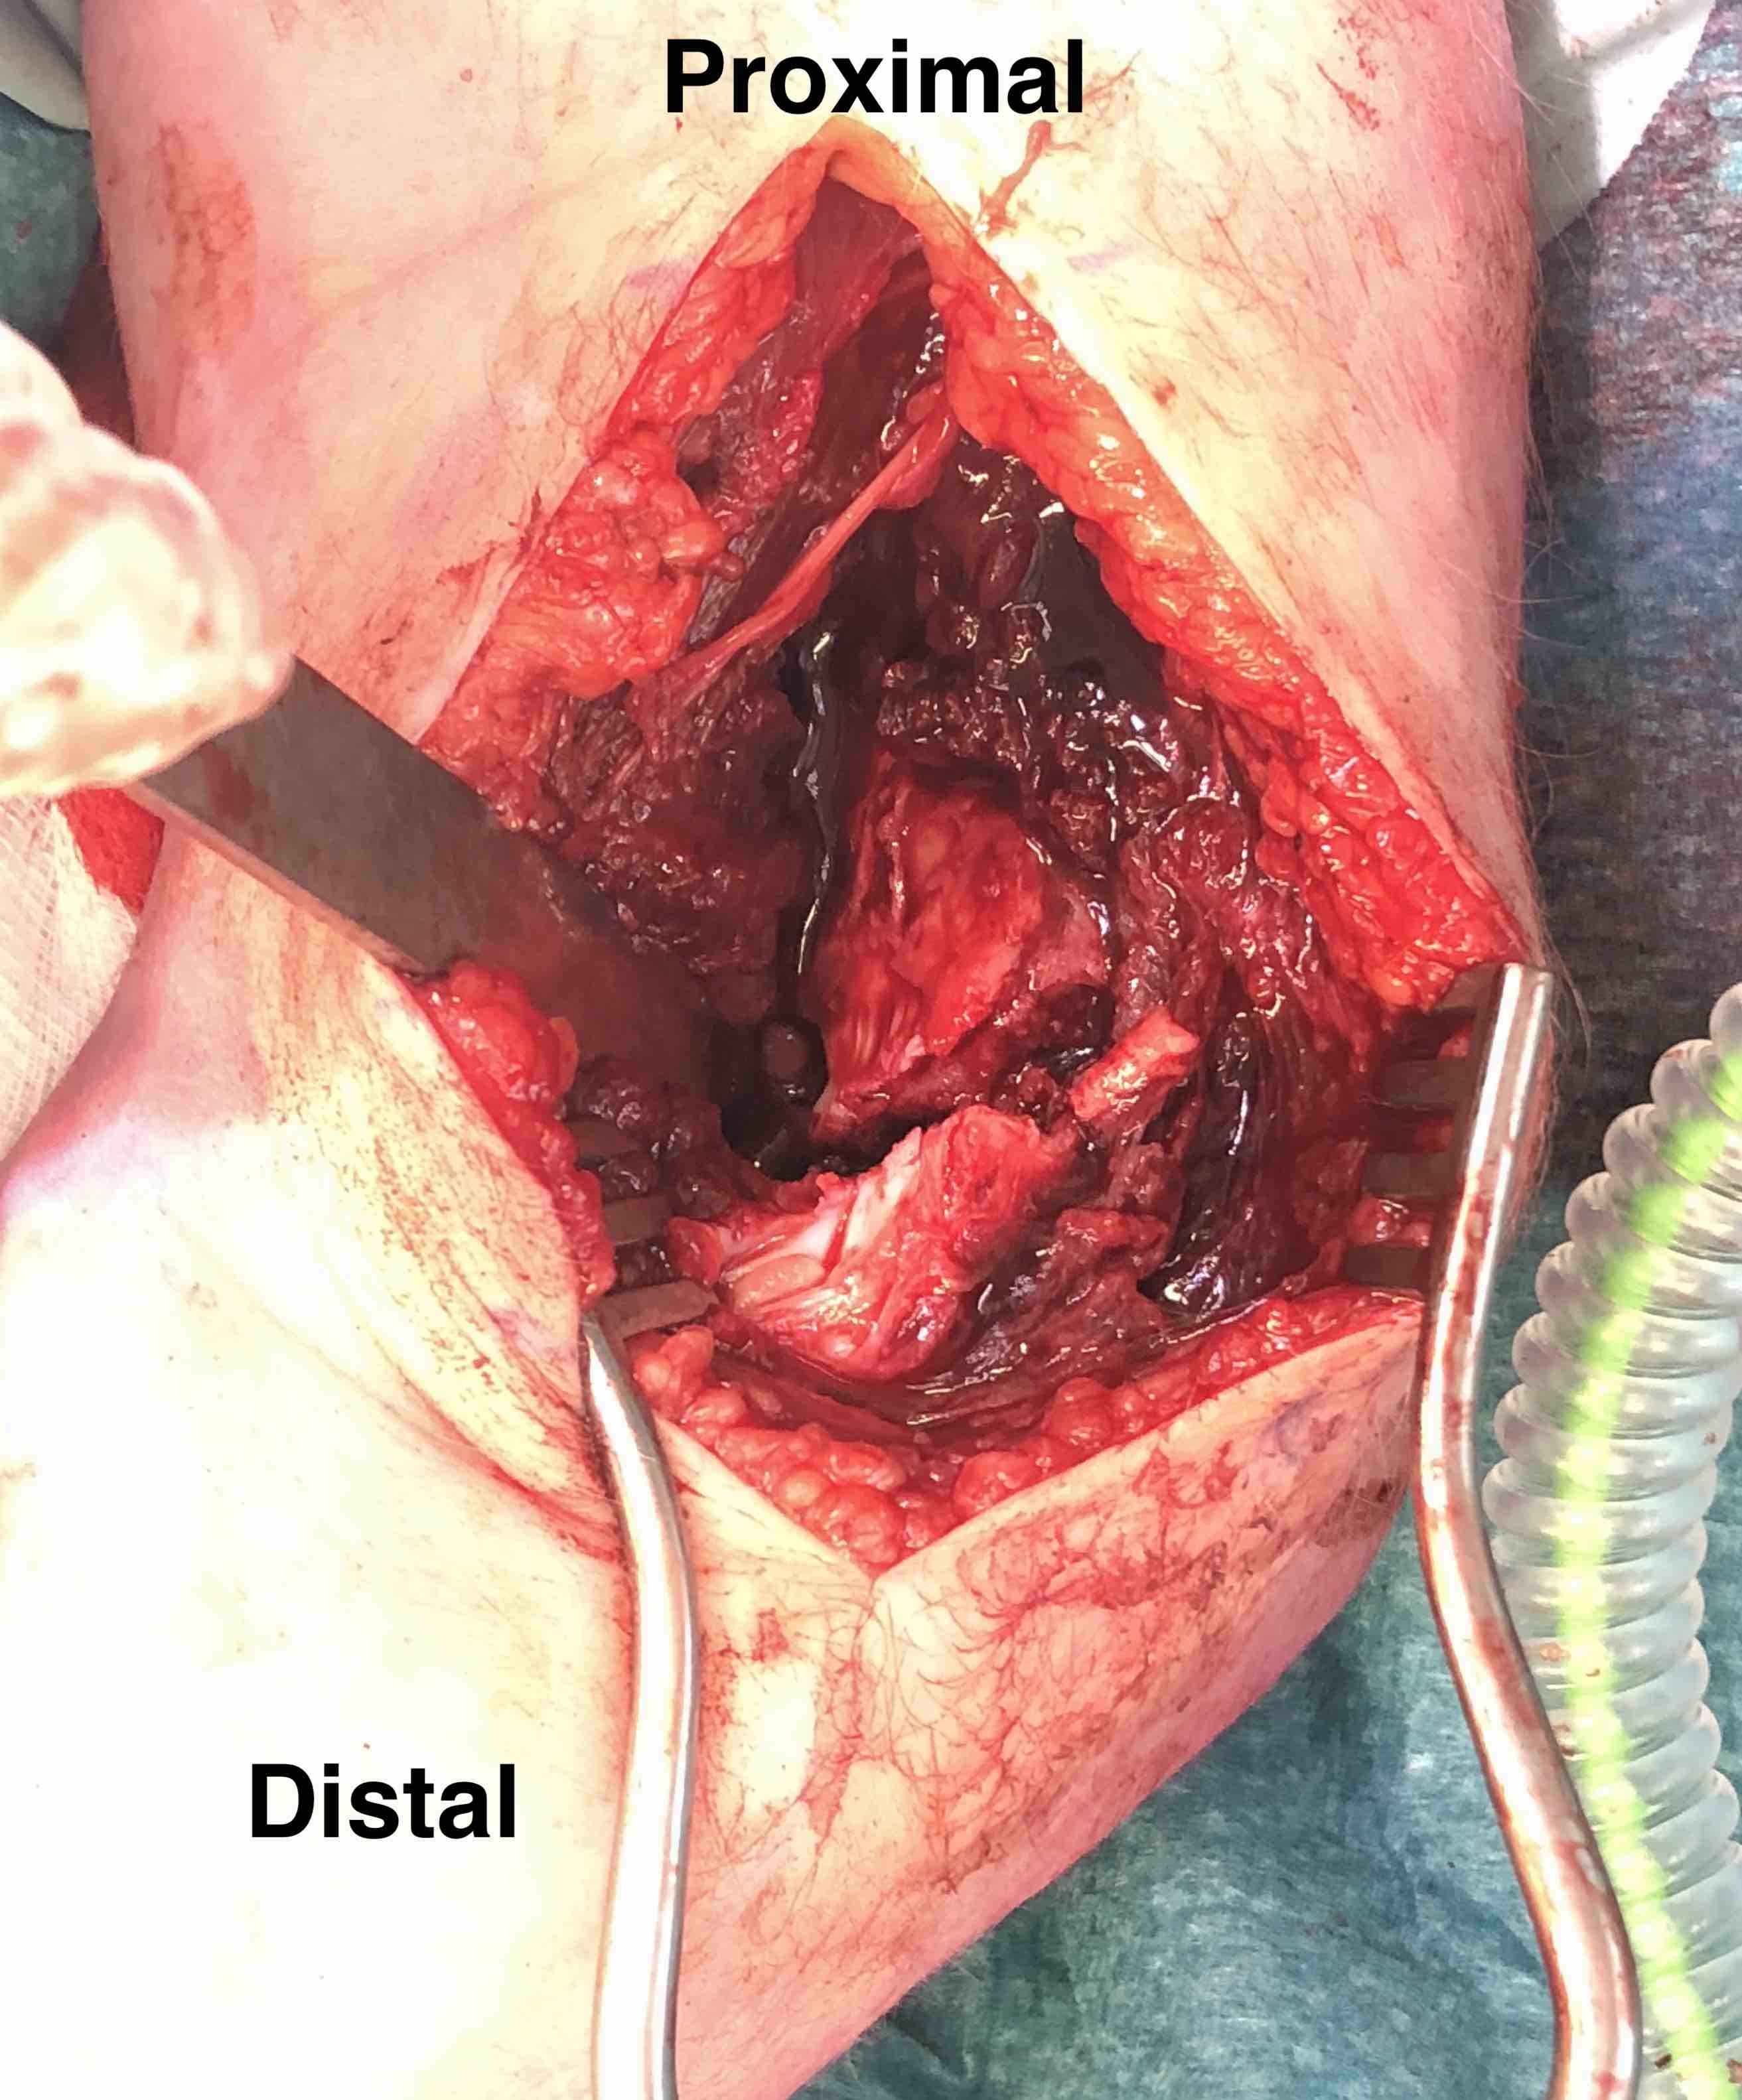

Lateral approach to distal humerus

- curved incision over lateral supracondylar ridge of humerus, and over proximal radius

- proximally intermuscular interval between brachioradialis & triceps

- proximally elevate brachioradialis and ECRL off the distal humerus

- distally split common extensor origin between ECRB and EDC and elevate anteriorly

Don't dissect posteriorly to protect blood supply

Don't need to dissect distal fragment

Use anterior homan retractor across distal humerus to elevate anterior capsule

- visualize distal joint line and perform anatomical reduction under vision

Open reduction of displaced lateral condyle in left elbow